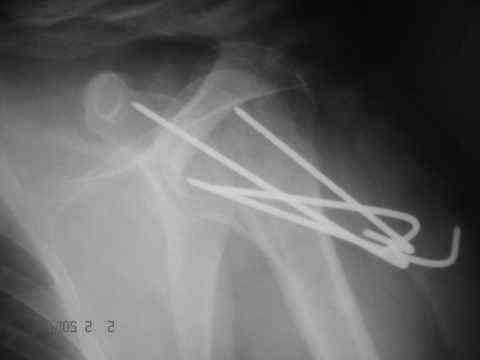

Looking at his previous x-rays, I was thinking of refixing the greater tuberosity, however got anaxillary view done today which was never done during this period and this shows non-union.

It looks like the initial injury was a head splitting fracture. Presently the patient has a non-union at the level of the anatomical neck with displaced tuberosities. I would tackle the non-union, and would try to replace the tuberosities, a difficult procedure. I would use the proximal humerus locking plate from the AO.

However, even if all goes well ( a big if!), the prognosis for regaining movement sufficient to tie his turban is poor.